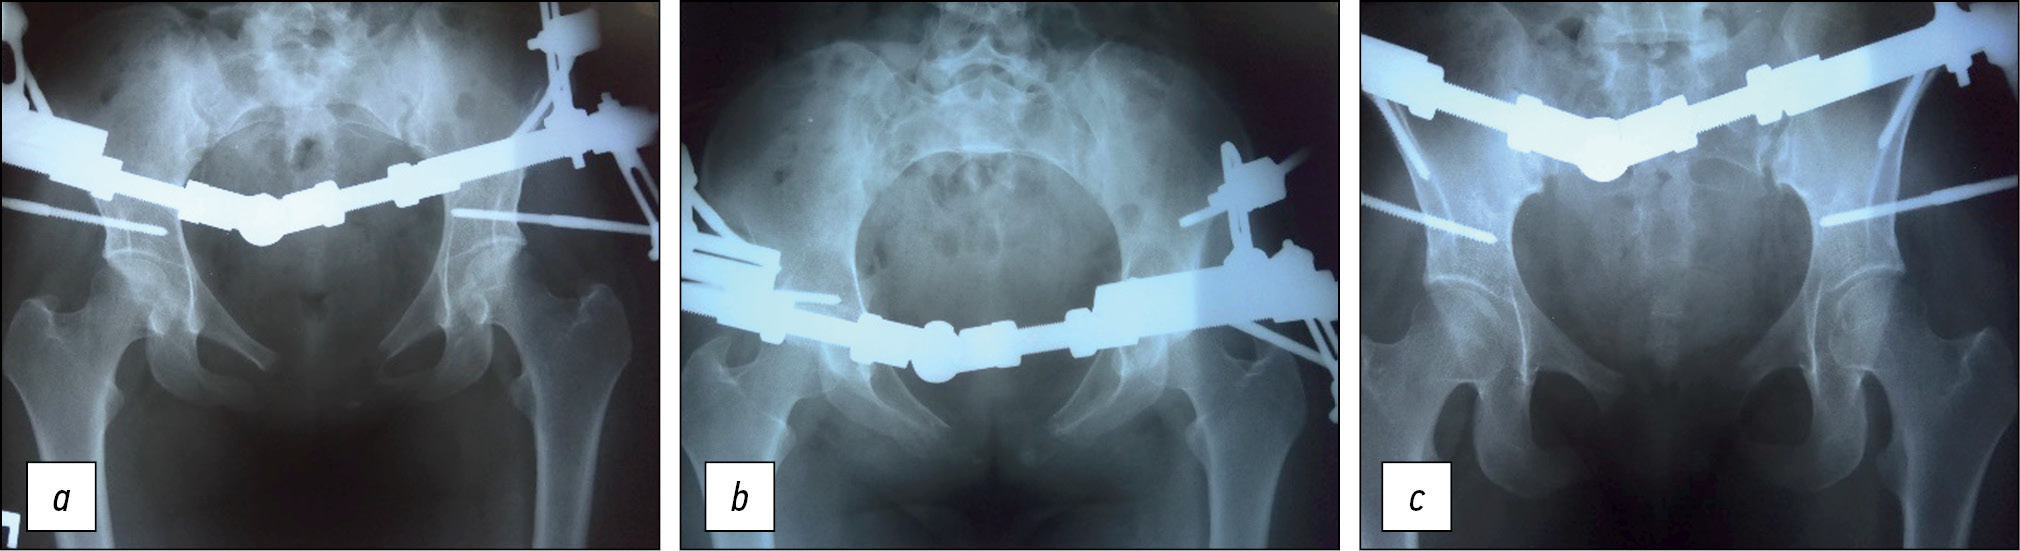

Рис. 2. Рентенограммы пациентки С. после операции тотальной резекции лонных ветвей, замещения дефекта пластическим материалом «КоллАпан-С», стабилизации тазового кольца аппаратом внешней фиксации стержневой конструкции Малахова–Кожевникова–Цуканова: а) прямая, b) каудальная, c) краниальная проекция.

Fig. 2. Radiographs of patient S. after surgery: total resection of the pubic rami, replacement of the defect with plastic material Kollapan S, stabilization of the pelvic ring with an external fixation device of the MCC rod structure: a) straight line; b) caudal; and c) cranial projections.